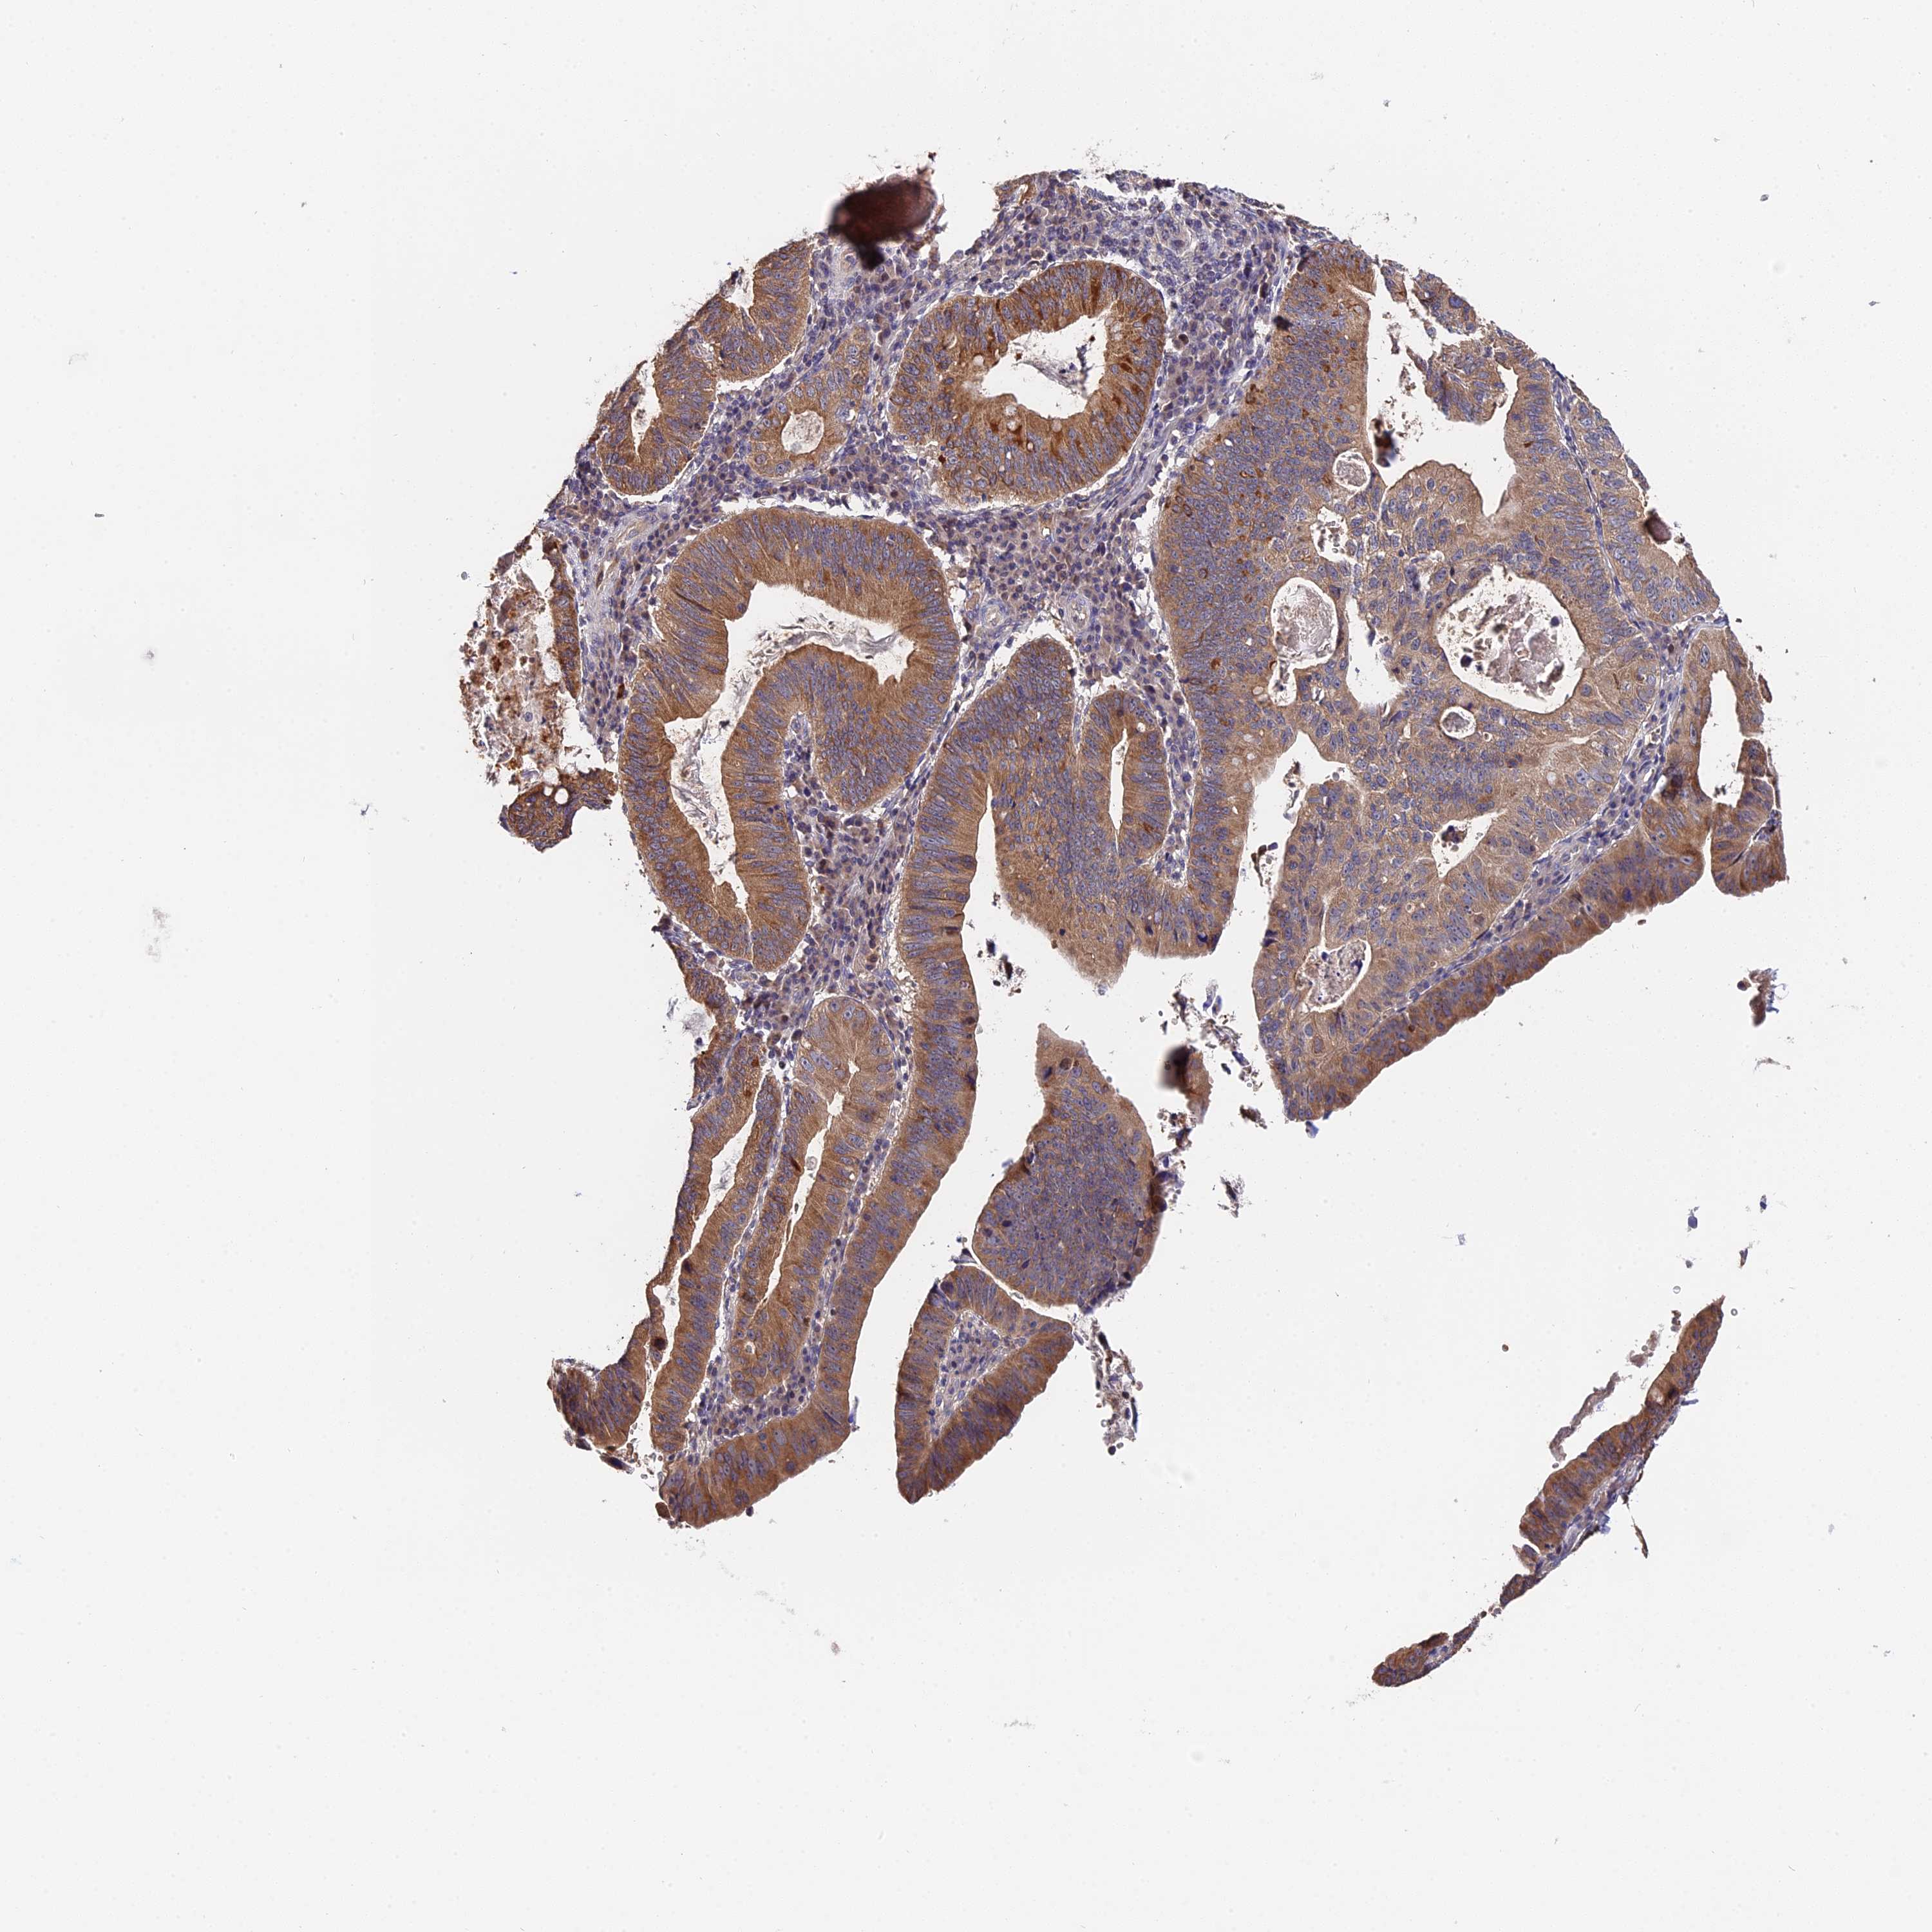

STOMACH CANCER - Protein expressioni

A mouse-over function shows sample information and annotation data. Click on an image to view it in a full screen mode. Samples can be filtered based on level of antibody staining by selecting one or several of the following categories: high, medium, low and not detected. The assay and annotation is described here.

Note that samples used for immunohistochemistry by the Human Protein Atlas do not correspond to samples in the TCGA dataset.

Antibody stainingi

Antibody staining in the annotated cell types in the current human tissue is reported as not detected, low, medium, or high, based on conventional immunohistochemistry profiling in selected tissues. This score is based on the combination of the staining intensity and fraction of stained cells.

Each image is clickable and will lead to virtual microscopy that enables deeper exploration of all samples and also displays staining intensity scores, fraction scores and subcellular localization as well as patient and tissue information for each sample.

Antibody HPA041130

Antibody HPA041380

Staining

High

Medium

Low

Not detected

Intensity

Strong

Moderate

Weak

Negative

Quantity

>75%

75%-25%

<25%

None

Location

Nuclear

Cytoplasmic/membranous

Cytoplasmic/membranous,nuclear

Adenocarcinoma, NOS